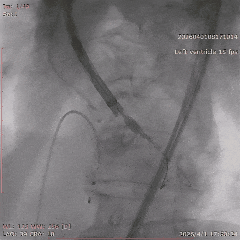

手术当天,团队顺利完成经导管主动脉瓣置换术。术中瓣膜释放位置理想,人工瓣膜功能良好,未见明显瓣周漏,也未出现严重传导阻滞、恶性心律失常等情况,患者术后安返CCU病房。

▲导丝跨瓣

▲18mm球囊预扩

▲输送器过弓

▲瓣膜定位

▲释放至工作位

▲工作位造影

▲脱钩

▲20mm球囊后扩

▲最终造影